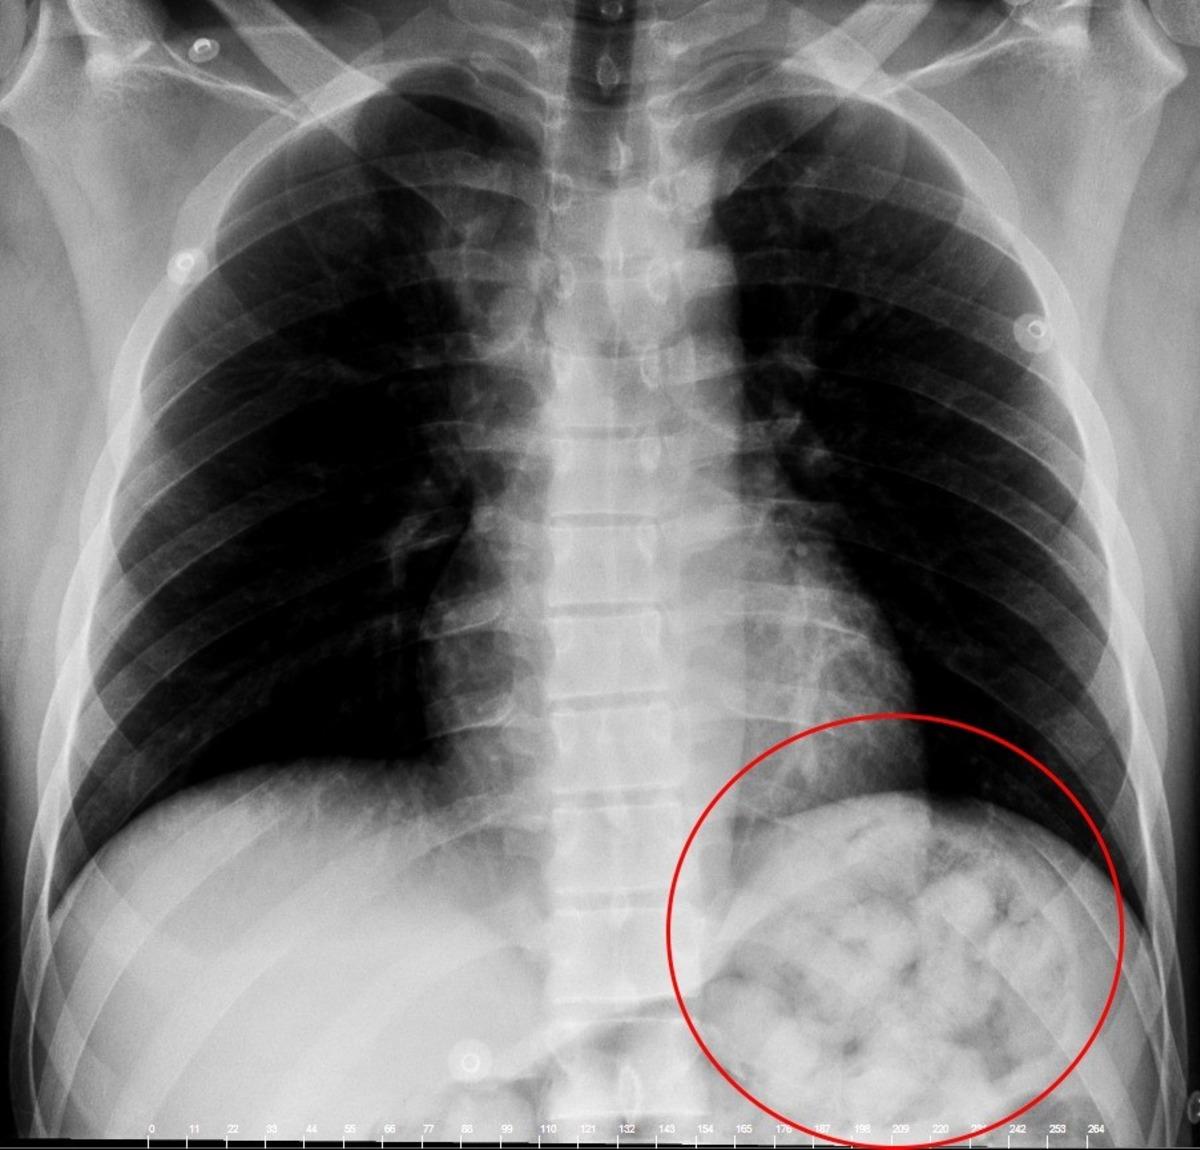

Edinilen bilgiye göre, 5 gün önce Van’dan otobüsle Ankara’ya gelen O. Zahed Ahmed Narziveh rahatsızlanınca hastaneye kaldırıldı. Ankara Şehir Hastanesine getirilen şahsın röntgen görüntüleri gerçeği ortaya çıkardı. Şahsın midesinde 890 gram ağırlığında 2’si patlamış halde 72 kapsül olduğu ve kapsüllerin patlaması ile fenalaştığı belirlendi. Mahkeme kararına istinaden ameliyata alınarak midesindeki metamfetamin kapsülleri çıkartılan zanlı, Ankara Emniyet Müdürlüğüne bağlı Narkotik Suçlarla Mücadele ekiplerince hastanedeki 5 günlük tedavisinin ardından adliyeye sevk edildi.